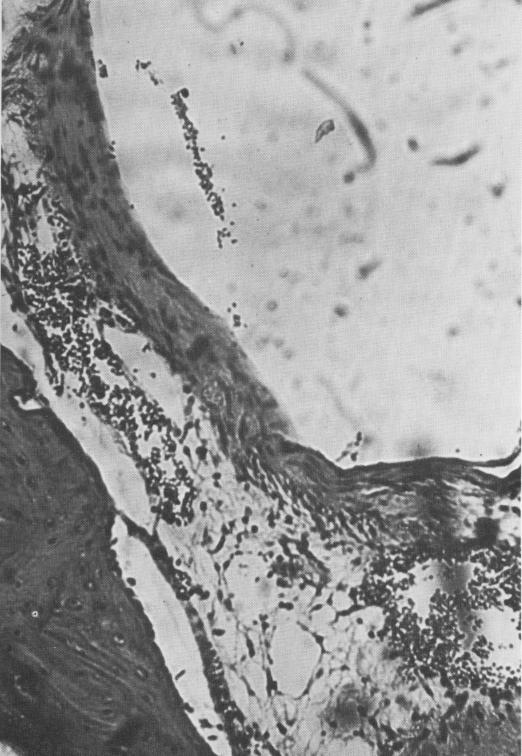

Fig. 4-69. Blood vessel formation appears near the base of the implant. The fatty marrow tissue looks normal. (Courtesy K. R. Blakey, Howard University.)

1 Blood vessel formation appears near the base of endosseous implant